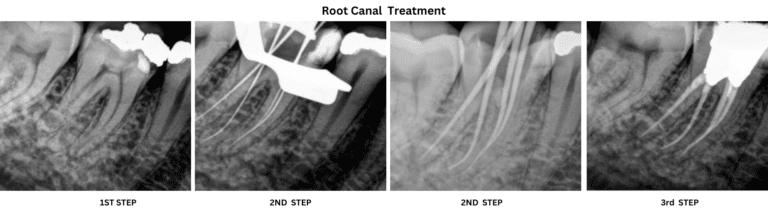

Step-by-Step Guide to Our Root Canal Procedure

At Aple Dentist Dental Clinic, we follow a step-by-step approach to our root canal procedure. This ensures that the treatment is thorough and effective in removing the infected pulp and preserving the tooth.

The first step is the initial consultation and diagnosis, where our root canal specialist will examine the affected tooth and determine if a root canal treatment is necessary. This may involve taking X-rays or using other diagnostic tools.

Once the diagnosis is confirmed, the next step is preparing the tooth for treatment. This involves administering local anesthesia to numb the area and ensure a painless procedure. The affected tooth is then isolated using a dental dam to keep it clean and dry.

The next step is accessing the infected pulp by creating a small opening in the tooth. The infected pulp is then removed using specialized tools, and the root canals are cleaned and shaped to remove any remaining bacteria.

After cleaning the root canals, they are filled with a rubber-like material called gutta percha to seal them and prevent reinfection. Finally, a temporary filling is placed on the tooth to protect it until a permanent restoration, such as a dental crown, can be placed.